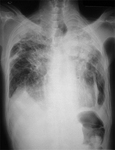

CXR showing changes consistent with simple silicosis or coal workers' pneumoconiosis

From the personal collection of Kenneth D. Rosenman, Michigan State University